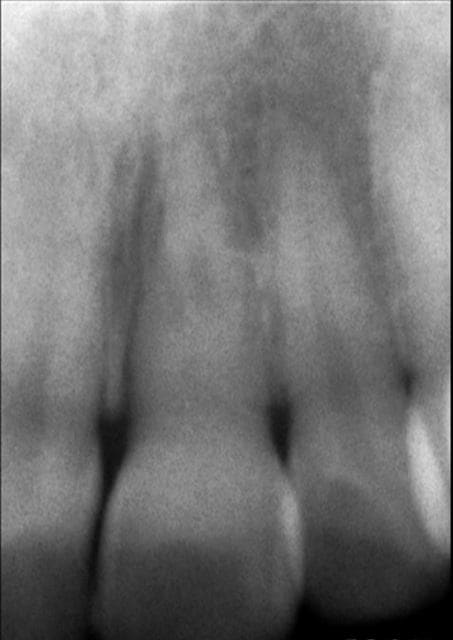

Bonjour, que me proposez vous pour cette jeune demoiselle de 21 ans....

Pas d'antécédent de choc, le canal a quasiment disparu radiologiquement, dent ne répondant pas aux tests de vitalité.

Rx 21 2015 07 20 ktufxm - Eugenol

Honnêtement tu oserais réaliser une endo sur une calcification pareil? Faut les avoir bien accroché!

disons qu'avec une vraie radio et pas une soupe de pixel on pourrait juger du canal.. la même bien accrochées, mes rétines ne suffisent pas..

Même si la radio n'est pas très nette, la photo est parlante. En l'absence de tout symptôme il serait suicidaire de tenter un traitement canalaire !